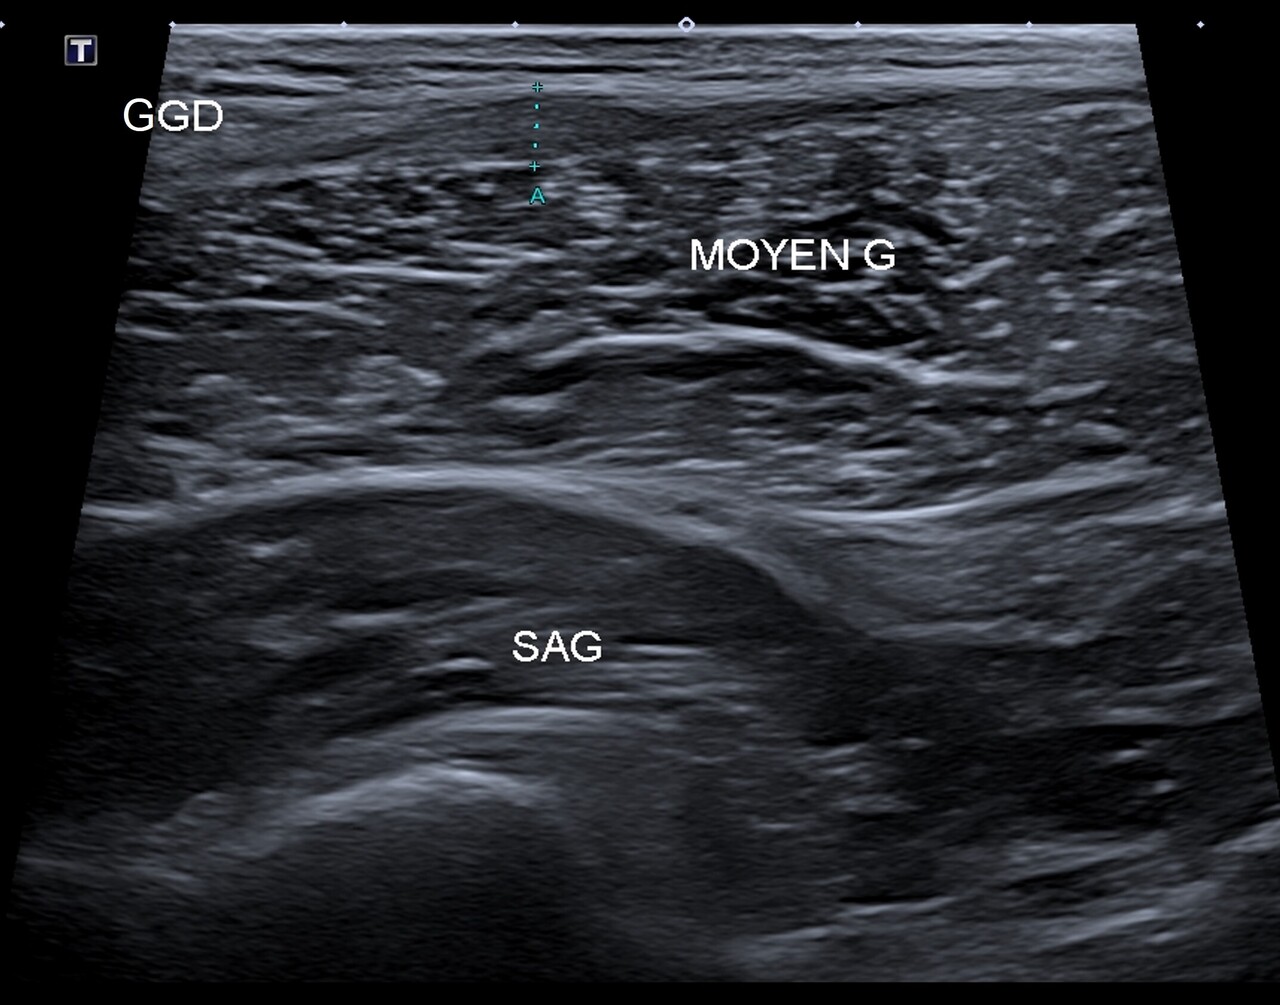

Une échographie musculaire est prescrite, avec consigne d’arrêter toute pratique sportive. L’examen met en évidence une lésion conjonctive intrinsèque de l’aponévrose du muscle grand glutéal classée stade 2 (fig. 2).